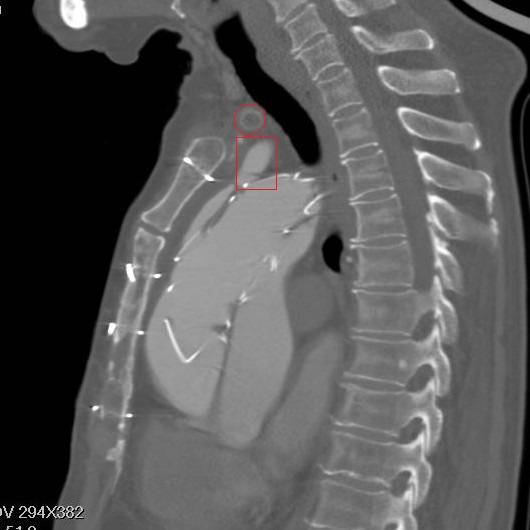

矢状面重建,胸骨钢丝很明显,方框示左颈总动脉,支架前端在假腔,后端在真腔。圆框示闭塞的人工血管

方框示左左锁骨下动脉,重度狭窄